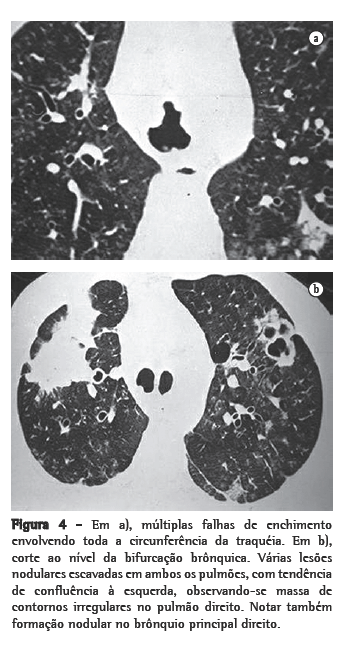

ResultadosNos 8 casos foram observadas na TC formações polipóides na traquéia. Em 1 deles, identificou-se também uma lesão em brônquio principal. Sete pacientes mostravam comprometimento do parênquima pulmonar. Em todos foram observadas lesões nodulares escavadas, com contornos internos irregulares, e paredes de espessuras variadas, com aspecto multilobulado em 6 casos, e com confluência das lesões em 5 deles (Figuras 1 a 5). Nódulos sólidos foram vistos em 6 pacientes, Em apenas 1 dos casos foram vistos níveis líquidos. As lesões predominaram nas bases em 3 pacientes, nos terços médios em 2, e em 2 não havia predomínio de distribuição. Em 1 dos pacientes, foi observada associação com massa, e em outro, com consolidação. Neste último paciente (Figura 5) foi constatada degeneração maligna em múltiplas lesões. Sinais de aprisionamento aéreo também foram observados em 1 caso. Em nenhum deles detectou-se linfonodomegalia ou derrame pleural.

A TC, particularmente com aquisição volumétrica (espiral), é superior às radiografias de tórax no reconhecimento de nódulos ainda pequenos, nas fases iniciais de disseminação pulmonar, por sua melhor caracterização e visualização de vegetações nodulares traqueobrônquicas. Os achados tomográficos incluem estreitamento nodular, focal ou difuso, da via aérea. Os nódulos crescem na superfície mucosa, e sua extensão intraluminar é melhor avaliada por TC.(3) São alterações facilmente correlacionadas à doença quando se dispõe da história clínica de papilomatose.(4) Outros achados relacionados à obstrução das vias aéreas e/ou infecções associadas são atelectasias, consolidações, aprisionamento aéreo e bronquiectasias.(2-4) Na nossa casuística, formações polipóides na traquéia foram observadas em todos os exames tomográficos. Sete pacientes mostravam comprometimento do parênquima pulmonar, caracterizado por lesões nodulares escavadas, com contornos internos irregulares, e paredes de espessuras variadas, com aspecto multilobulado e tendendo à confluência. Nódulos sólidos foram vistos em 6 pacientes. Em nenhum deles detectou-se linfonodomegalia ou derrame pleural.